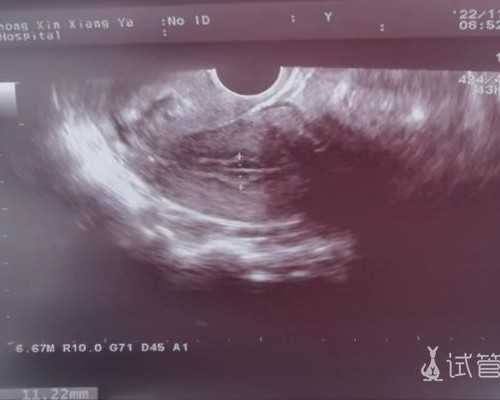

医生在b超的引导下,用特制的取卵针通过阴道穿刺成熟卵泡,将卵子吸出。取卵通常在静脉麻醉下进行,因此女性不会感受到穿刺过程带来的疼痛。

胚胎移植后14天测定血清HCG以确定是否怀孕。胚胎移植后21天再次测定血清HCG,了解胚胎发育情况。胚胎移植后30天进行阴道超声检查,确定是否有宫内妊娠及胎心搏动。